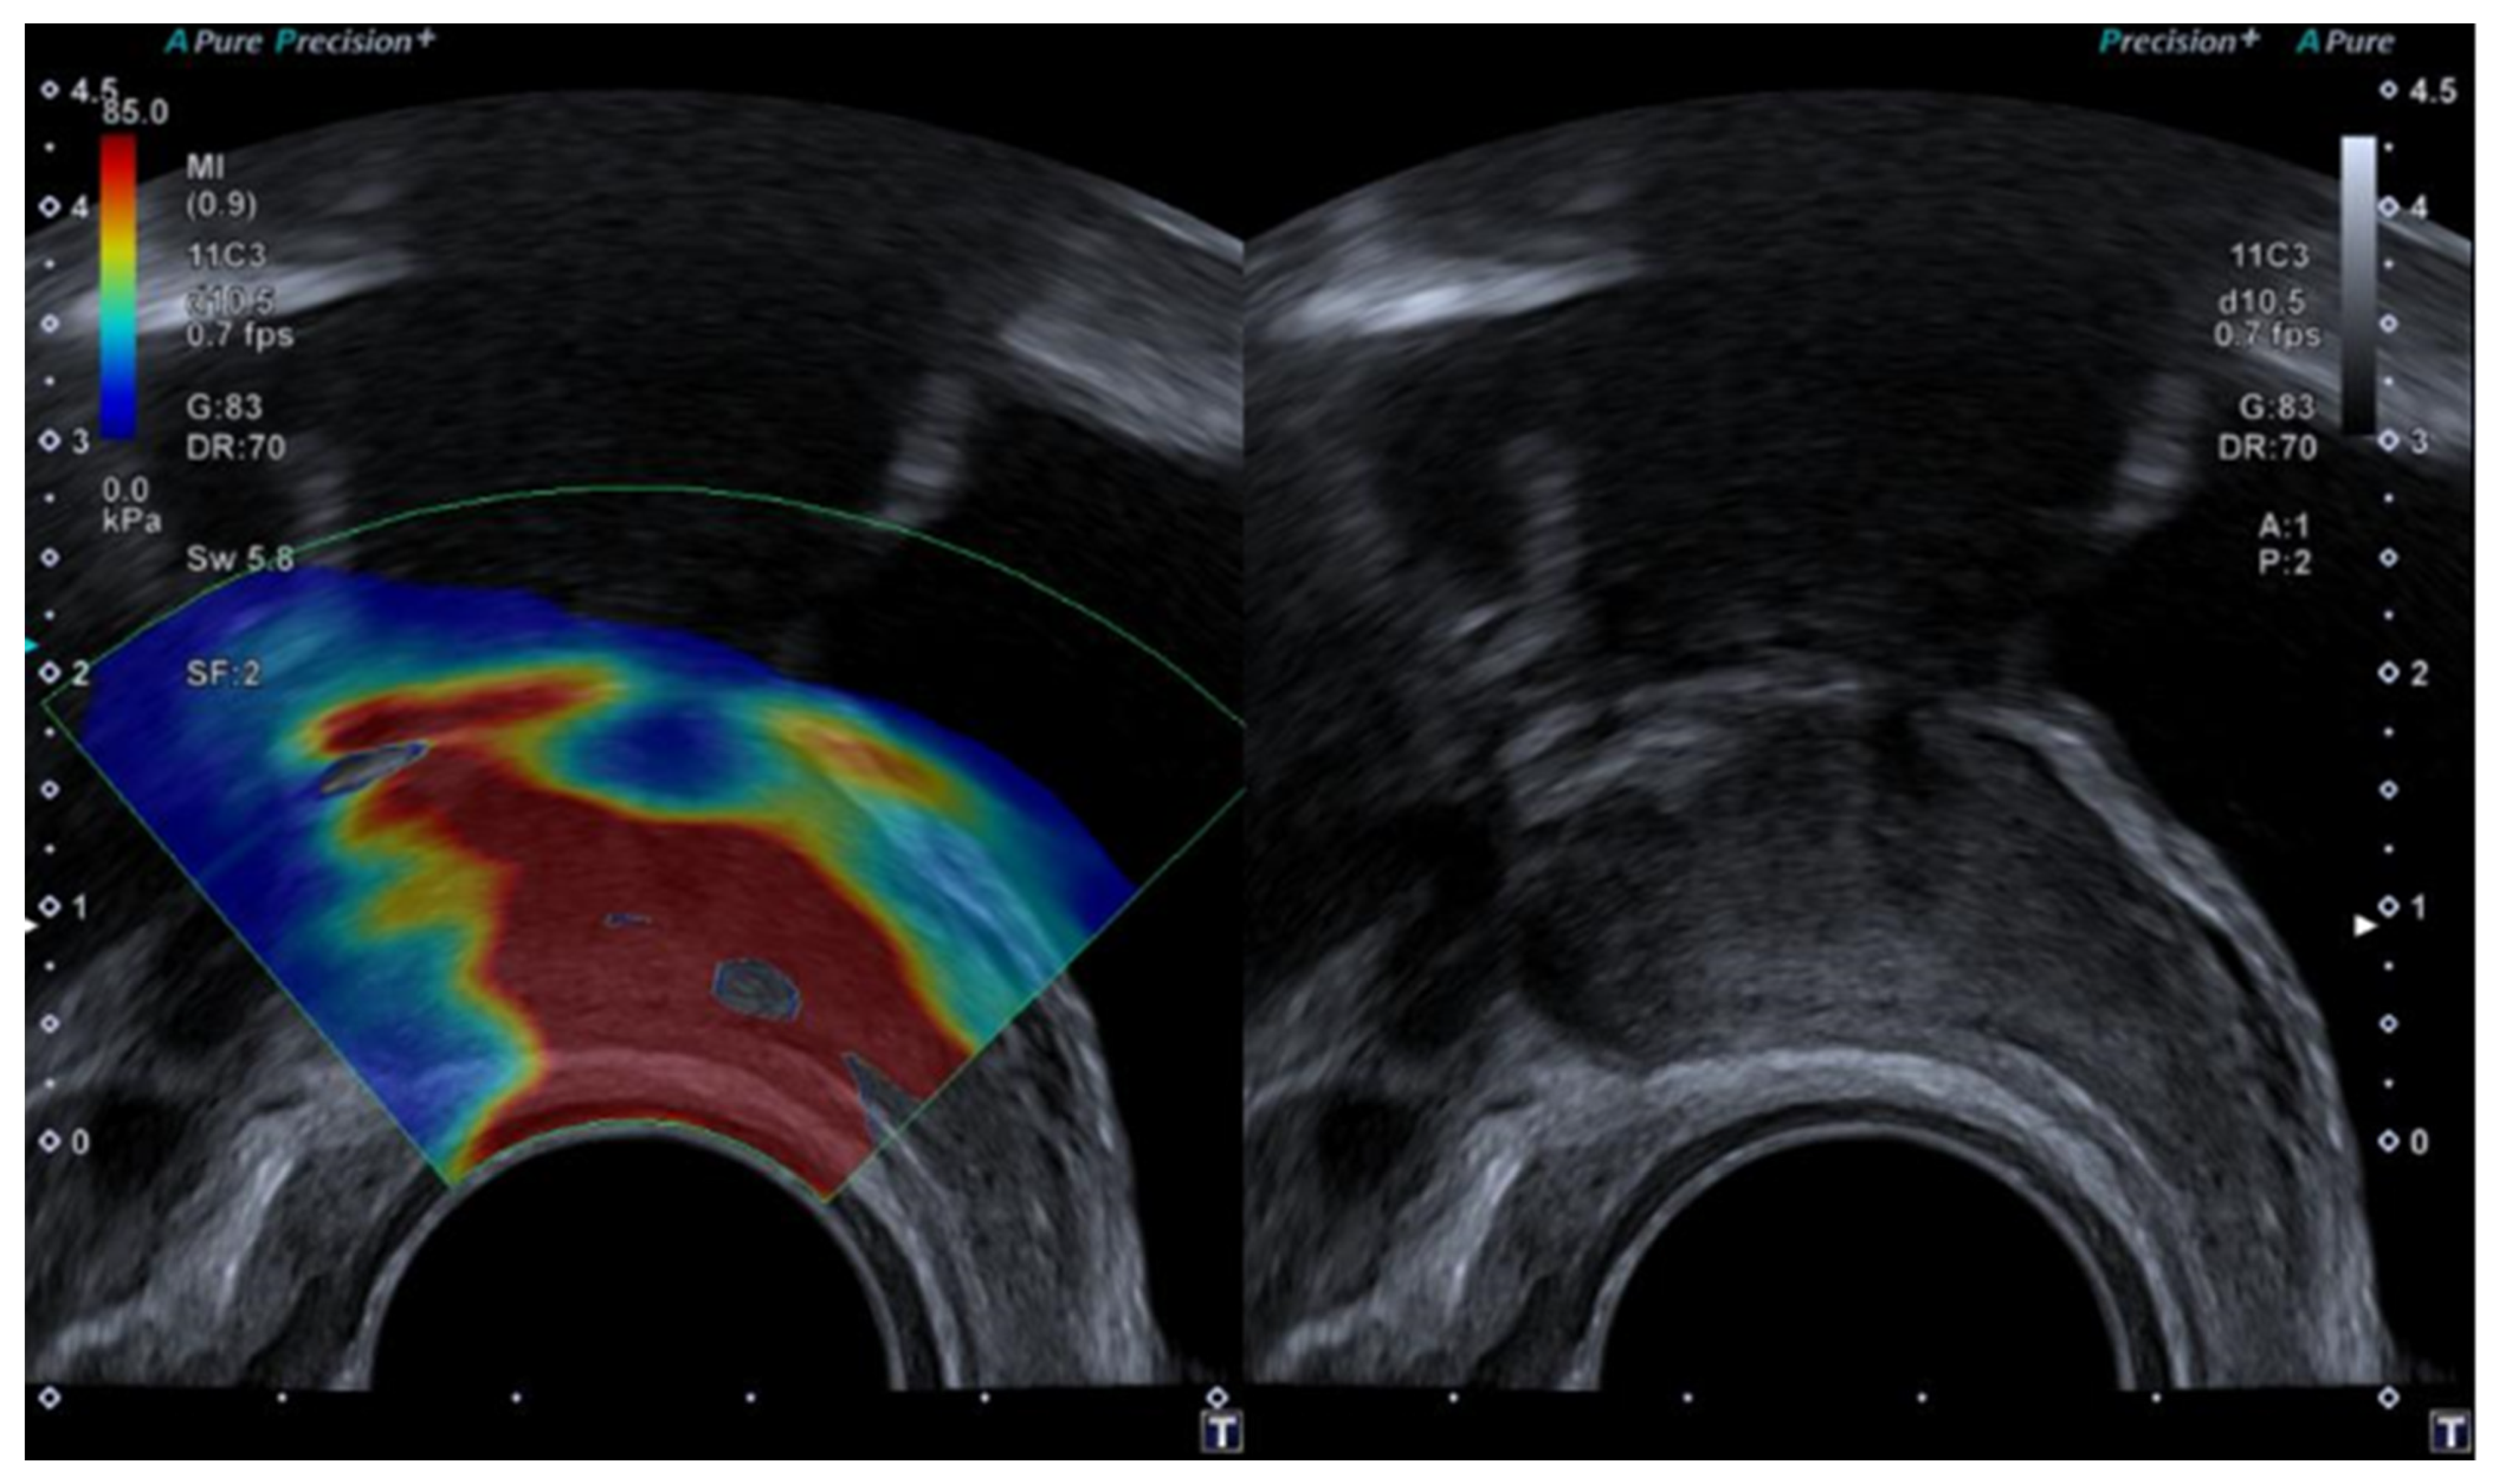

Figure 2.

SWE ultrasound showing a t3b tumour in a 70-year-old female.

SWE uses a push pulse to induce shear waves, and an elastogram is created by monitoring shear wave speed through the tissue. The transducer is held still, without applying pressure to the tumour area, for approximately 5–10 s until a satisfying elastogram is created on the monitor. A region of interest (ROI) may be placed covering the entire lesion or placed within the stiffest areas of the tumour. The elastography index is reported as either the mean or the maximal value of the ROI. SWE may also be interpreted using a visual colour scale [29,30,31,32].

Several cut-off values have been suggested for both SE and SWE (see Table 1); however, it is important to keep in mind that the elastography value differs depending on the technical approach, equipment, and software used, as well as intra- and inter-variation between operators.